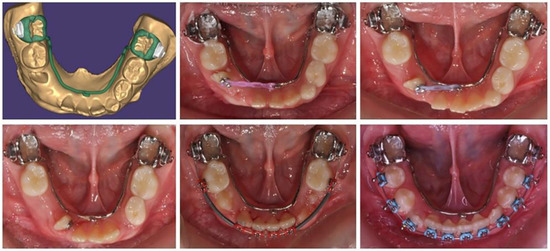

Based on the patient’s digital model, a lingual arch design was made with a hook in suitable location and direction to ensure the desired tooth movement of the lower-right lateral incisor (Figure 2). The body of the PDaA was maximally reduced, but at the same time, it was stable enough to be an anchorage. The patient adapted to it in a short period of time, and the biomechanical system used showed a good result.

After the surgical exposure of the upper-right first molar, the PDaA was bonded and molar traction started (Figure 4). When the position of the molar changed, part of the ladder was removed, so that the bearing area changed along with the movement of the tooth.

For the purposes of orthodontic treatment, the extraction of two upper premolars (14 and 25) is required, which will provide a space exactly equal to the crowding size (the sizes of the right lateral and left premolar). It was not desirable to design a biomechanical system which would involve the medial displacement of the distal anchorage teeth, as this occurs with the classic distal displacement of canines and anchorage second premolar and first molar (anchorage type A). In this clinical case, a stable distal anchorage zone was required, which could be provided by mini-orthodontic implants or a rigid transpalatal arch involving all available anchorage teeth (Figure 8). When fabricating this type of digitally planned arch, elements were incorporated into its design to aid in a more bodily movement of the canines, which would reduce the inclination side effects of their movement.

The PDaA construction includes first and second molar rings, right second premolar lingual wall, first molar tube and an extended right first molar hook for a higher level of applied canine distalizing force.

Figure 2. Treatment progress in insertion of a lower-right lateral in the dental arch, using a lingual arch support.

Figure 4. Laser-sintered metal PDaA during the orthodontic traction of the upper-right first molar. In green is the digital design of the appliance is represented.

Figure 8. Transpalatal support arch with extension for the distal movement of maxillary right canine—treatment progress. In blue is the digital design of the PDaA.